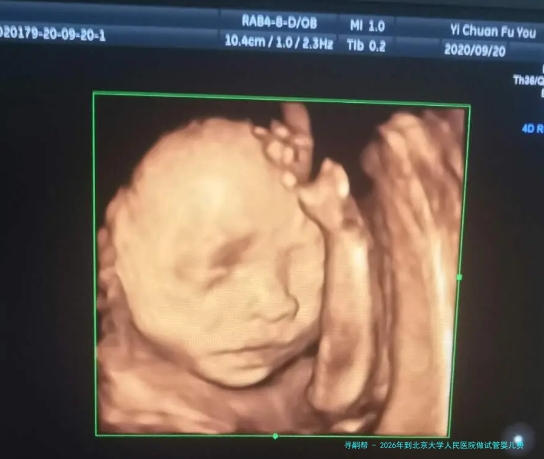

北京试管婴儿 北京助孕费用 2026-01-22·31人浏览 北京第三代试管婴儿费用明细曝光,快来了解具体要多少在北京谋求生育希望的家庭们,至于第三代试管婴儿(PGT)的费用无疑是关注的核心。这个先进的辅助生育技术,为众多遗传病症携带体、高龄或复发性流产的夫妻带来了福音。根据我们对北京地区众多家权威生殖中心的认知,现在在北京进行一次完善的第三代试管婴儿周期,其总价格大约在1两万到20万人民币之间,甚至根据各别情况和检测需求可能更高。

北京试管婴儿 北京助孕费用 2026-01-20·33人浏览 北京市三代试管助孕费用大概多少钱,2026各项费用全面汇总!面对生育的挑战,许多家庭将目光投向了人类辅助生殖技术,其中第三代试管婴儿(PGT,即是胚胎移植前遗传学检测)以其特别的优势,为特定个体群带来了新的期望。然而,在北京这座国际大城市进行三代试管婴儿助孕,其高昂的费用往往是准父母们最为关怀的问题其中之一。本文将为您详细梳理2026年北京市三代试管婴儿的各项费用组成,并提供1个全面的费用估算,帮助您更明了地计划生育之路。